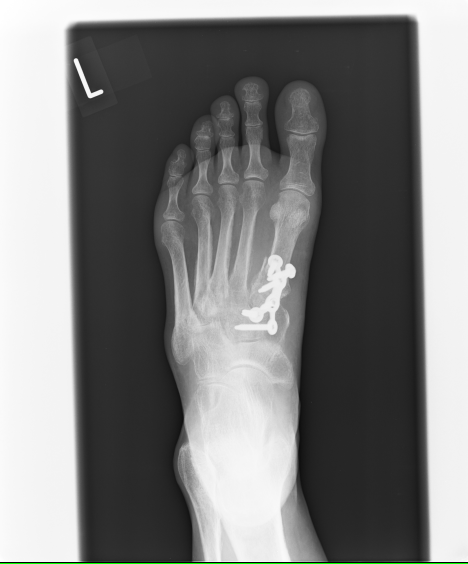

〇リスフラン脱臼骨折

折れた骨と関節をビスで固定する手術をしました。

手術は成功していますが、その後のギプスが足に合わず圧迫を受けていました。

夜も眠れないほどの痛みは処置後の悪循環によるものと思われます。

皆さんは骨折してるのだから痛いのは当り前だと思い込んでいますが、何週も経過して夜眠れないほどの痛みは悪循環そのものです。

適切な処置が行われていれば苦しむことはありません。